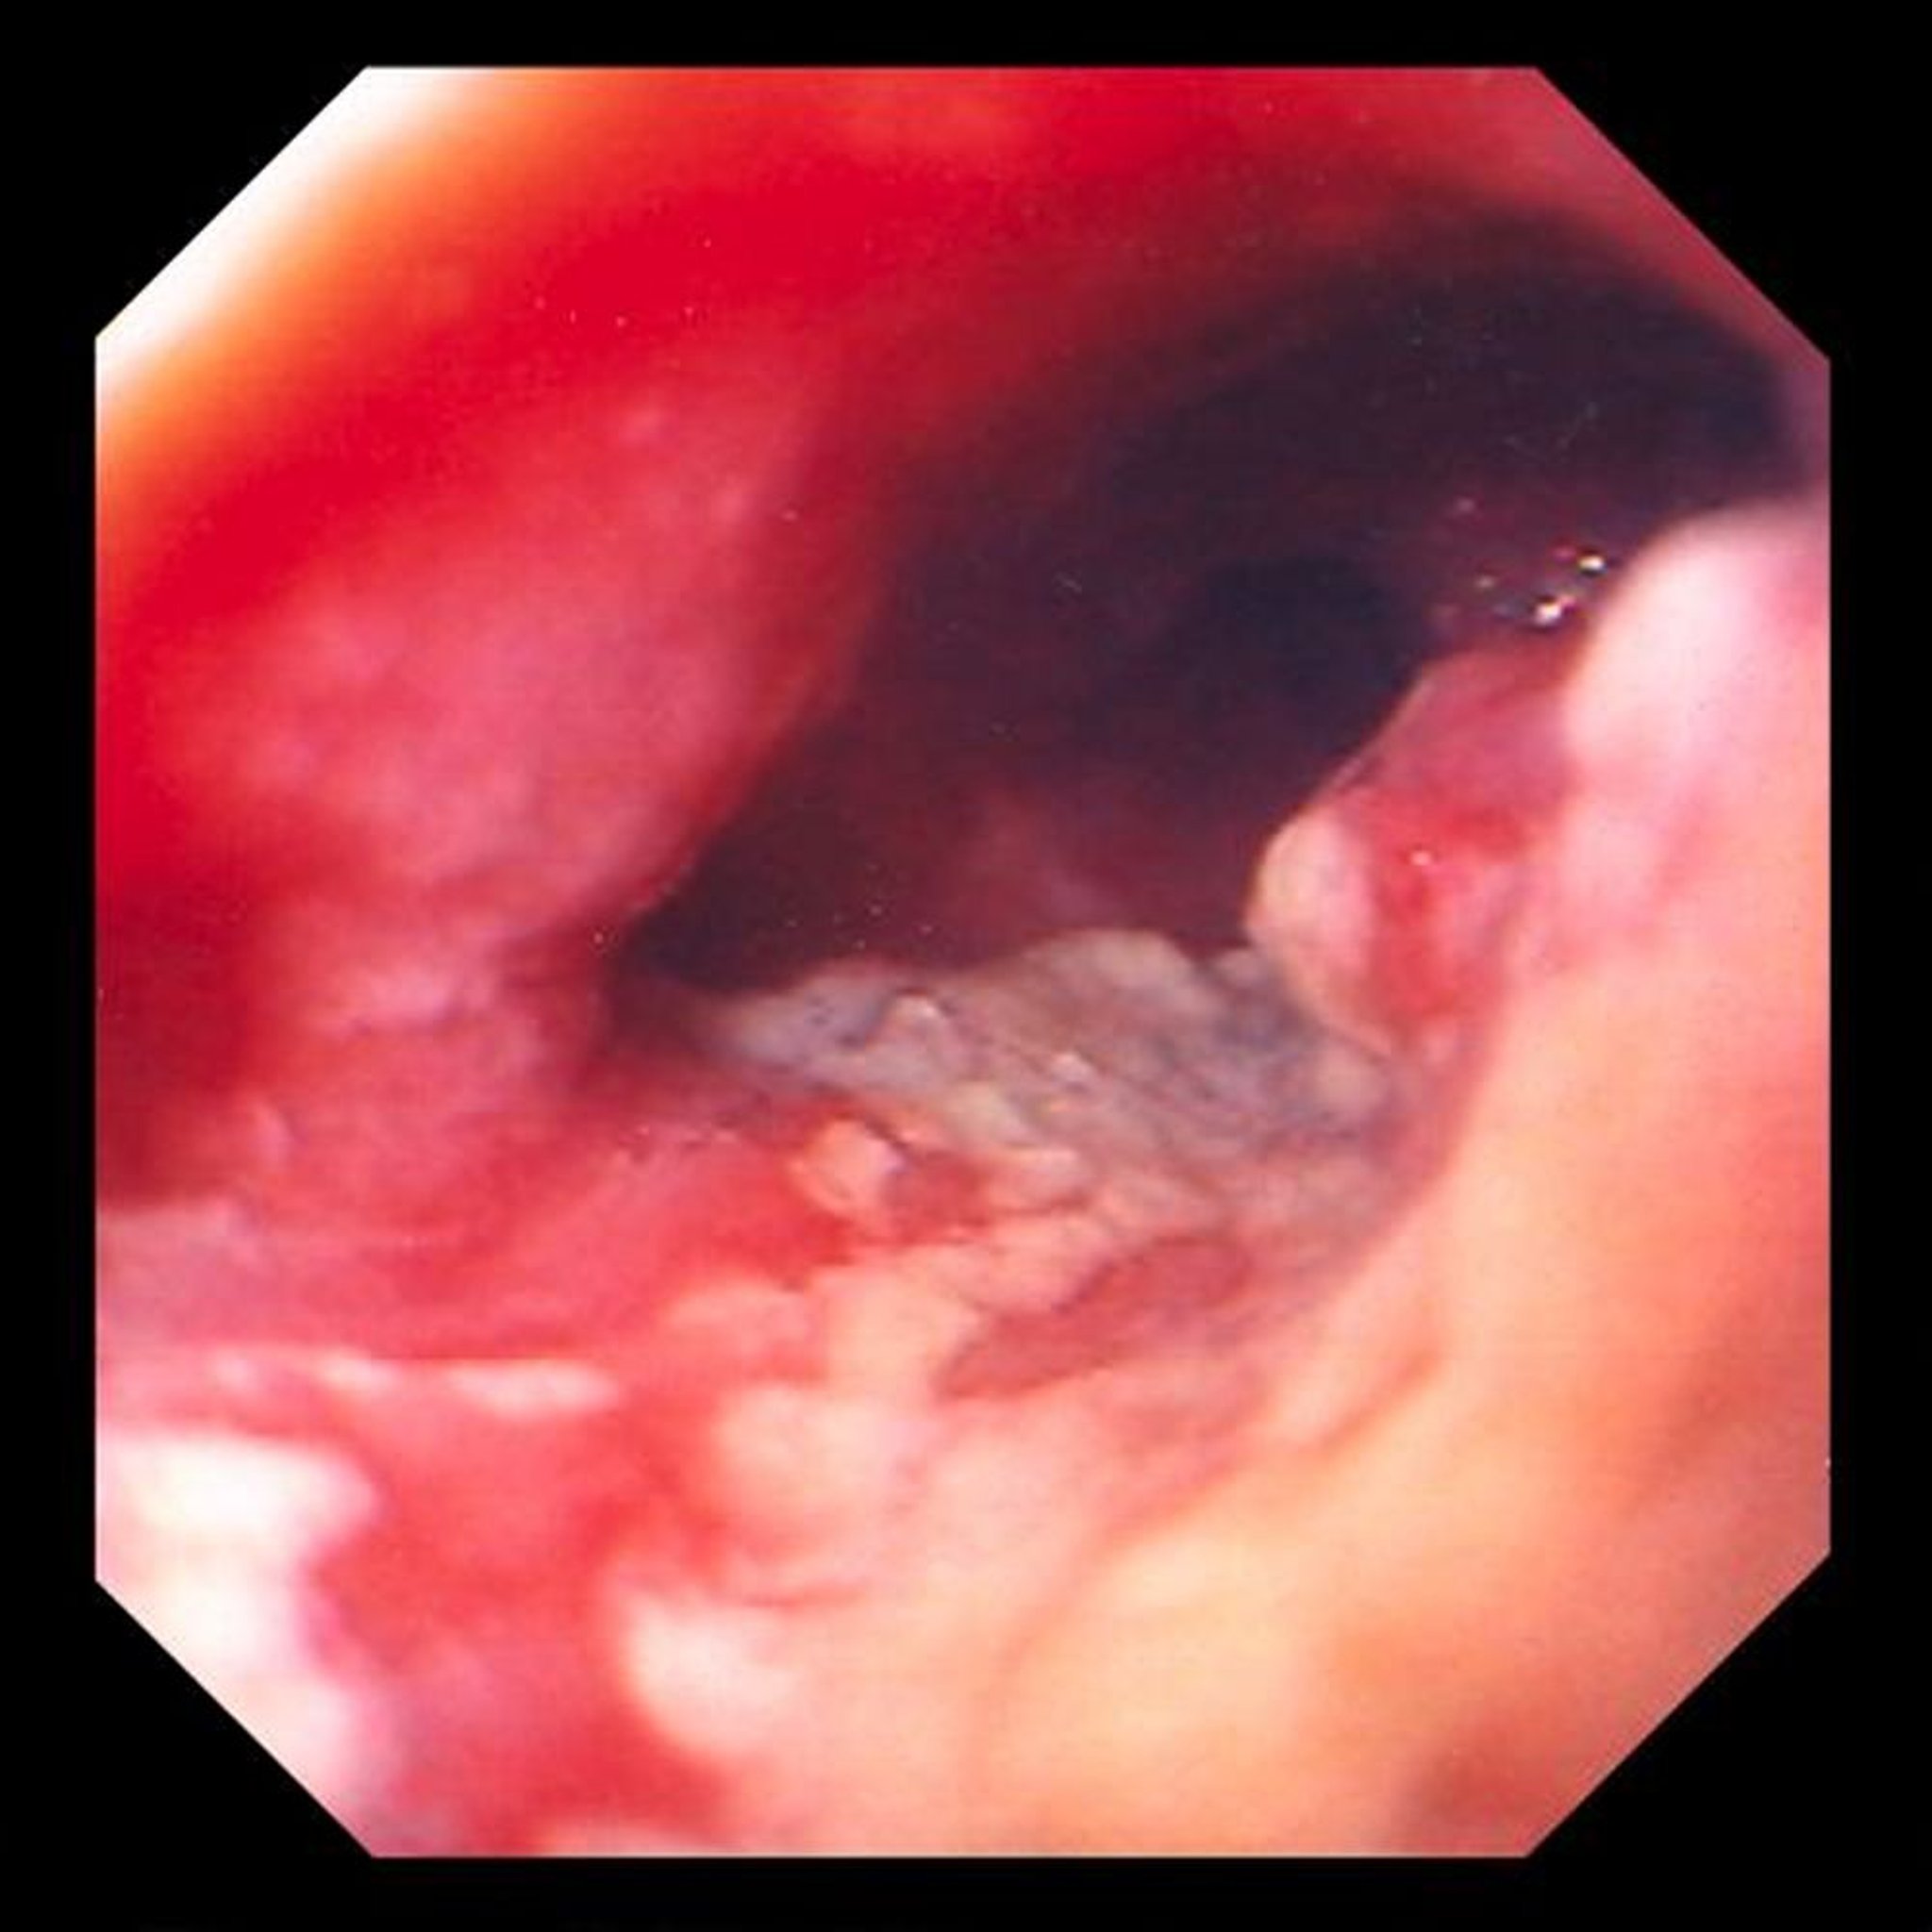

Adenokarzinom des Ösophagus

Dieses Bild zeigt einen ulzerierten, einschnürenden Tumor im distalen Ösophagus, der stark auf ein Adenokarzinom hindeutet, das aus metaplastischen säulenförmigen Veränderungen (Barrett-Ösophagus) entsteht.

Image provided by David M. Martin, MD.